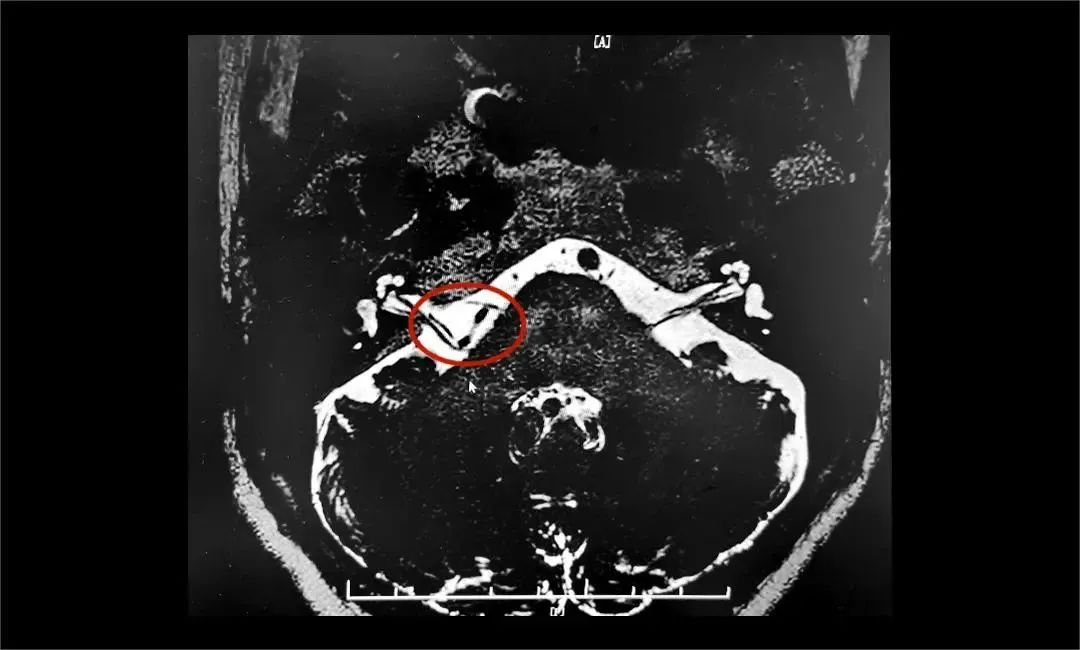

為進(jìn)一步治療,王阿姨在家人陪伴下慕名求醫(yī)楊忠旭博士。楊忠旭博士認(rèn)真評(píng)估王阿姨面肌痙攣發(fā)生的頻率、強(qiáng)度和持續(xù)時(shí)間,并完善了核磁顱神經(jīng)檢查。面神經(jīng)MRTA+增強(qiáng)顯示:右側(cè)面神經(jīng)與周圍小血管關(guān)系密切。

▲ 右側(cè)面神經(jīng)與周圍小血管關(guān)系密切

楊忠旭博士認(rèn)為,患者藥物治療效果不佳,癥狀反復(fù)發(fā)作,已影響日常生活,手術(shù)指征明確,未見(jiàn)明顯手術(shù)禁忌癥。在告知患者及家屬手術(shù)風(fēng)險(xiǎn),取得家屬同意后,楊忠旭教授團(tuán)隊(duì)為患者實(shí)施了神經(jīng)電生理監(jiān)測(cè)下微血管減壓術(shù)。